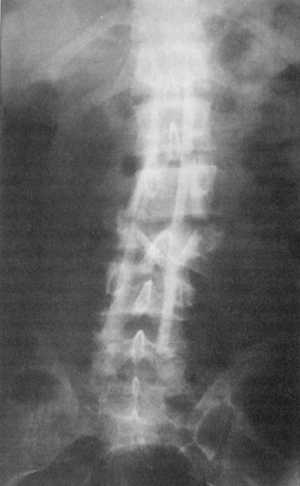

методов исследования. Важным в этом плане является рентгенологическое исследование,

позволяющее установить характер повреждения костно-суставного компонента,

что имеет значение при выборе лечебной тактики. Самым достоверным рентгенологическим

признаком компрессионного перелома позвонка является клиноподобная его деформация

(84,6%) причем вершина клина чаще всего повернута кпереди, реже встречается

боковая компрессия (16,4%). Иногда отмечается переднебоковая компрессия тела

Оптимальной проекцией для диагностики раздробленного перелома является передне-задняя

рентгенограмма, на которой выявляется смещение ножки дуги позвонка кнаружи

от боковой стенки канала позвоночника. Щели суставов деформированы, приобретают

клиноподобную форму, иногда значительно зияют, края суставных фасеток не совпадают.